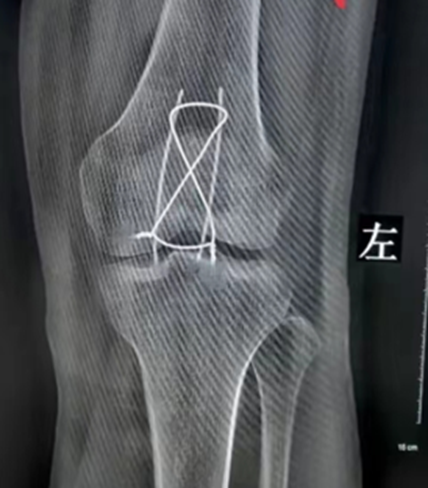

我们在临床康复治疗过程中,经常会听到这样的对话。那么骨折损伤术后到底该不该动,该怎么动呢?来听听专业康复治疗师的怎么说。

在骨折术后,医生通常会让患者制动休息,但是,长期卧床也不可取,适时进行功能锻炼可防止废用性的肌肉萎缩和关节粘连,促使早日恢复功能。在伤后早期2周内,此时患肢肿胀、疼痛,康复训练的主要形式是患肢肌肉的等长收缩和物理因子治疗。伤后2周至骨折临床愈合,此期除继续做患肢的肌肉收缩训练外,可在康复治疗师的帮助下,逐渐恢复骨折端上下关节的活动,进行适当的功能训练,并逐渐由被动活动转为主动活动,以防止邻近关节的关节僵硬;在病情允许下,应尽早起床进行全身活动。